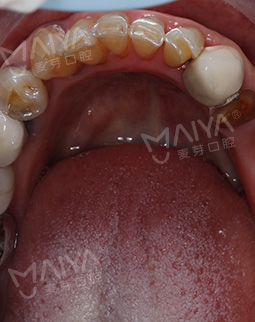

距离我上次做种牙手术,又一个多月了。今天来院复诊,“现在,我的牙好了,整个人精神面貌也恢复了,种回一口好牙,现在不仅恢复了身体健康,还找回了缺牙前那种想吃就吃的好心情,什么果什么肉随便吃,消化好吃嘛嘛香!”复查时,肖阿姨激动地说。虽然要来医院进行牙齿维护,但是为了我的牙齿健康,还是得坚持,毕竟牙齿陪伴一生,没有了它吃什么都没味道。真的非常感谢麦芽给了我再尝美味的机会。

今天来院种牙,肖阿姨满心欢喜地来到麦芽口腔,赵院长仅花了不到两个小时就为她种好了牙齿,种完牙后,肖阿姨竖起了大拇指:"种牙一点都不痛,打麻醉也很到位,用的针很小,我这么瘦都没什么感觉,胖一点更不会有。没有想象中可怕,整个过程很快,我也很放松,赵院长技术真的非常棒,术后没有不适感。"如今,肖阿姨看上去仿佛年轻了10岁,有了牙齿能够享口福了,生活也更加滋润。"现在有口福了,出去旅行才有意义。"说起种牙的愿望,肖阿姨说道。